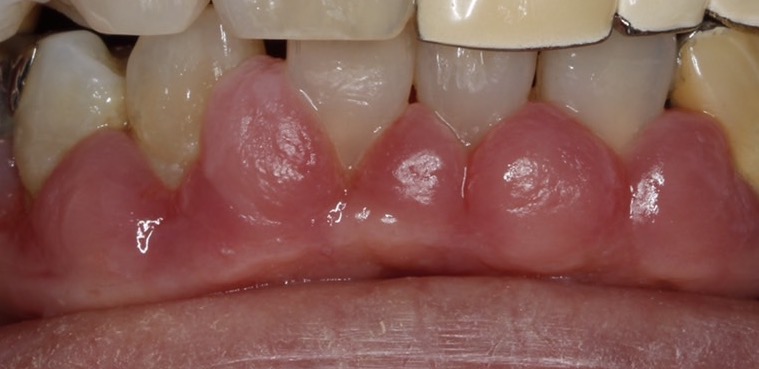

歯磨きをしたら血が出てきた。鏡を見たら歯茎が赤く腫れている、ズキズキとした痛みがある…。など歯茎(歯肉)が腫れた事はお口の中のトラブルの中でも特に多くの方が経験している症状の一つではないでしょうか?

2,歯周病、歯肉炎;歯肉炎は、歯垢(プラーク)や歯石の細菌が原因で起こります。ブラッシング不足などでプラークが蓄積すると歯肉の炎症が生じます。炎症が生じると歯肉の腫れや易出血が起ります。この段階の腫れはしっかりブラッシングを行う事で消失していきます。しかし、この状態を放置すると歯周炎に移行していきます。歯周炎に移行してしまうと歯茎からの排膿や出血が生じます。この状態ではブラッシングを行ってもあまり改善しません。専門的なクリーニングや抗生物質の服用が必要となって来ます。

薬の副作用;高血圧に用いられる降圧剤(カルシウム拮抗薬)・抗てんかん薬・免疫抑制薬といった薬の副作用でも、歯肉の増殖が起きる事があります。この歯肉増殖が起きた場合、ブラッシングが出来なくなり結果的に歯肉の腫れが生じます。薬物による歯肉増殖では基本的には薬の変更しかありません。薬の変更後、それでも治らない場合は歯肉の切除が必要となってきます。